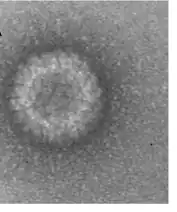

The virus particle, like other coltiviruses, is about 80 nm in diameter and is generally not enveloped. The double-stranded RNA viral genome is about 20,000 bp long and is divided into 12 segments, which are termed Seg-1 to Seg-12. Viral replication in infected cells is associated with characteristic cytoplasmic granular matrices. Evidence suggests the viral presence in mature erythrocytes is a result of replication of the virus in hematopoetic erythrocyte precursor cells and simultaneous maturation of the infected immature cells rather than of direct entry and replication of CTFV in mature erythrocytes.[15]